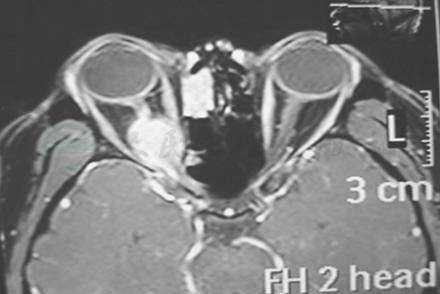

CT扫描能显示受累骨骨质破坏性改变和眼眶内软组织肿块(图6)。

图6 MRI轴位扫描T1WI显示右眼眶尖高信号肿块,斜坡骨质破坏(箭头示)